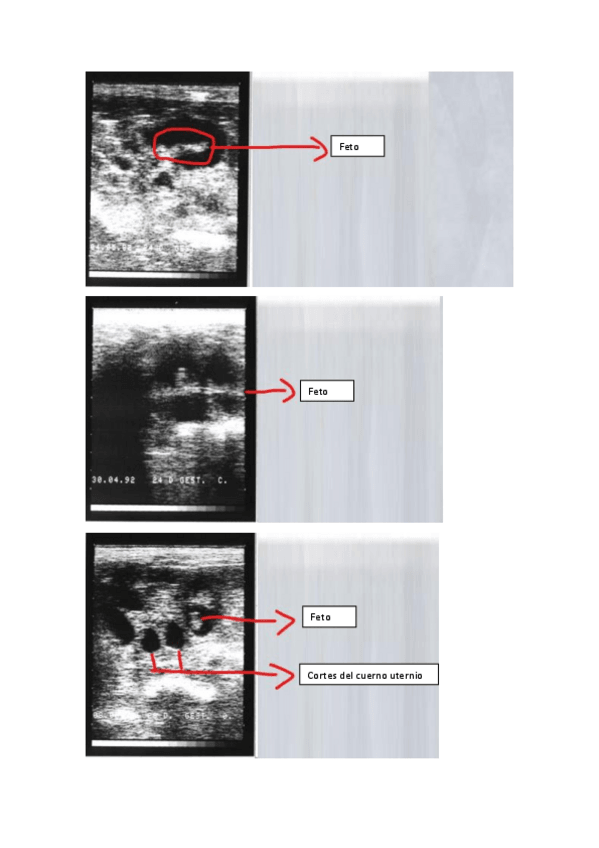

He publicado nuevos practicas de 3º Reproduccion y Fund. Obstetricos: Fundamentos-del-diagnostico-ecografico-en-reproduccion-animal.pdf